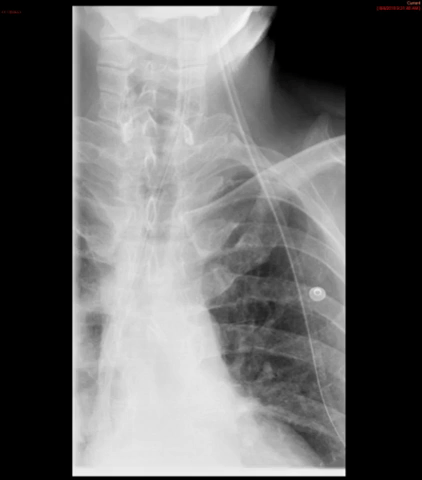

- The technologist will obtain a scout radiograph(s) to include the chest and upper abdomen to determine the location of the surgical chain sutures or surgical staples

(key image 1).

- The esophagogastric anastomosis is usually located at the level of the aortic arch or just below it.

- The technologist will then obtain a post-procedure overhead of the chest.

(key image 7).